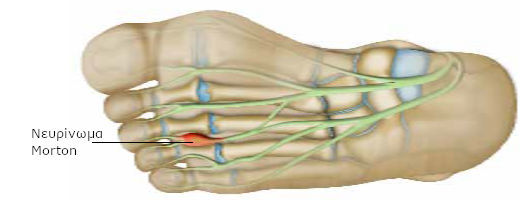

Ορισμένα νεύρα, που περνούν ανάμεσα από τους δακτύλους και ευθύνονται για την αισθητικότητά τους (αισθητικά νεύρα) συμπιέζονται.

Τα νεύρα μπορεί να συμπιέζονται είτε από τα μετατάρσια, είτε από τους θυλάκους που προφυλάσσουν την άρθρωση από τριβές (ορογόνοι θύλακοι). Ο θύλακος μπορεί να ερεθιστεί, λόγω πιέσεων (ορογονοθυλακίτιδα), να γεμίσει υγρό, να αυξηθεί ο όγκος του και να συμπιέσει το νεύρο.

Τα νεύρα περιβάλλονται από μια προστατευτική θήκη. Όταν το νεύρο πιέζεται, αμύνεται αυξάνοντας το πάχος της θήκης. Όσο όμως πραγματοποιείται πάχυνση της θήκης, τόσο οι ιστοί στο εσωτερικό συμπιέζονται και επιδεινώνεται η κατάστασή τους. Τότε εμφανίζονται οι πόνοι. Στο σημείο συμπίεσης, το νεύρο παρουσιάζει, μερικές φορές, διόγκωση. Πρόκειται για νευρίνωμα Morton. Στην ιατρική γλώσσα, το πρόβλημα αυτό αναφέρεται ως μεταταρσιαλγία Morton.

Υπάρχει μεγαλύτερος κίνδυνος εμφάνισης του προβλήματος, εάν φοράτε στενά υποδήματα, ιδιαίτερα στις άκρες, καθώς οι δάκτυλοι «στριμώχνονται». Συνήθως η πάθηση πλήττει τις γυναίκες από 20 έως 50 ετών.